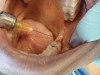

2. The angled handpiece of the CO2 laser was held perpendicular to the target lesion (Figure 4), and the ablation of the inflamed tissue began (Figure 5). The dental surgeon was careful to avoid contact between the laser beam and the tooth enamel. Note: In this case, the inflamed tissue was located distally from the involved molar. There was no direct contact of the beam with the tooth, as the surgeon was careful not to hit the enamel. However, if an operculum covers part of the tooth, an adaptive tool (for example, a wax spatula) needs to be inserted between the tissue and the tooth to prevent possible damage. For an inexperienced CO2 laser surgeon, it is important and highly recommended to always shield the tooth during the procedure.6

Fig 4. The angled handpiece of the CO2 laser was held perpendicular to the target lesion.

Figure 4

Fig 5. The ablation of the inflamed tissue began.

Figure 5